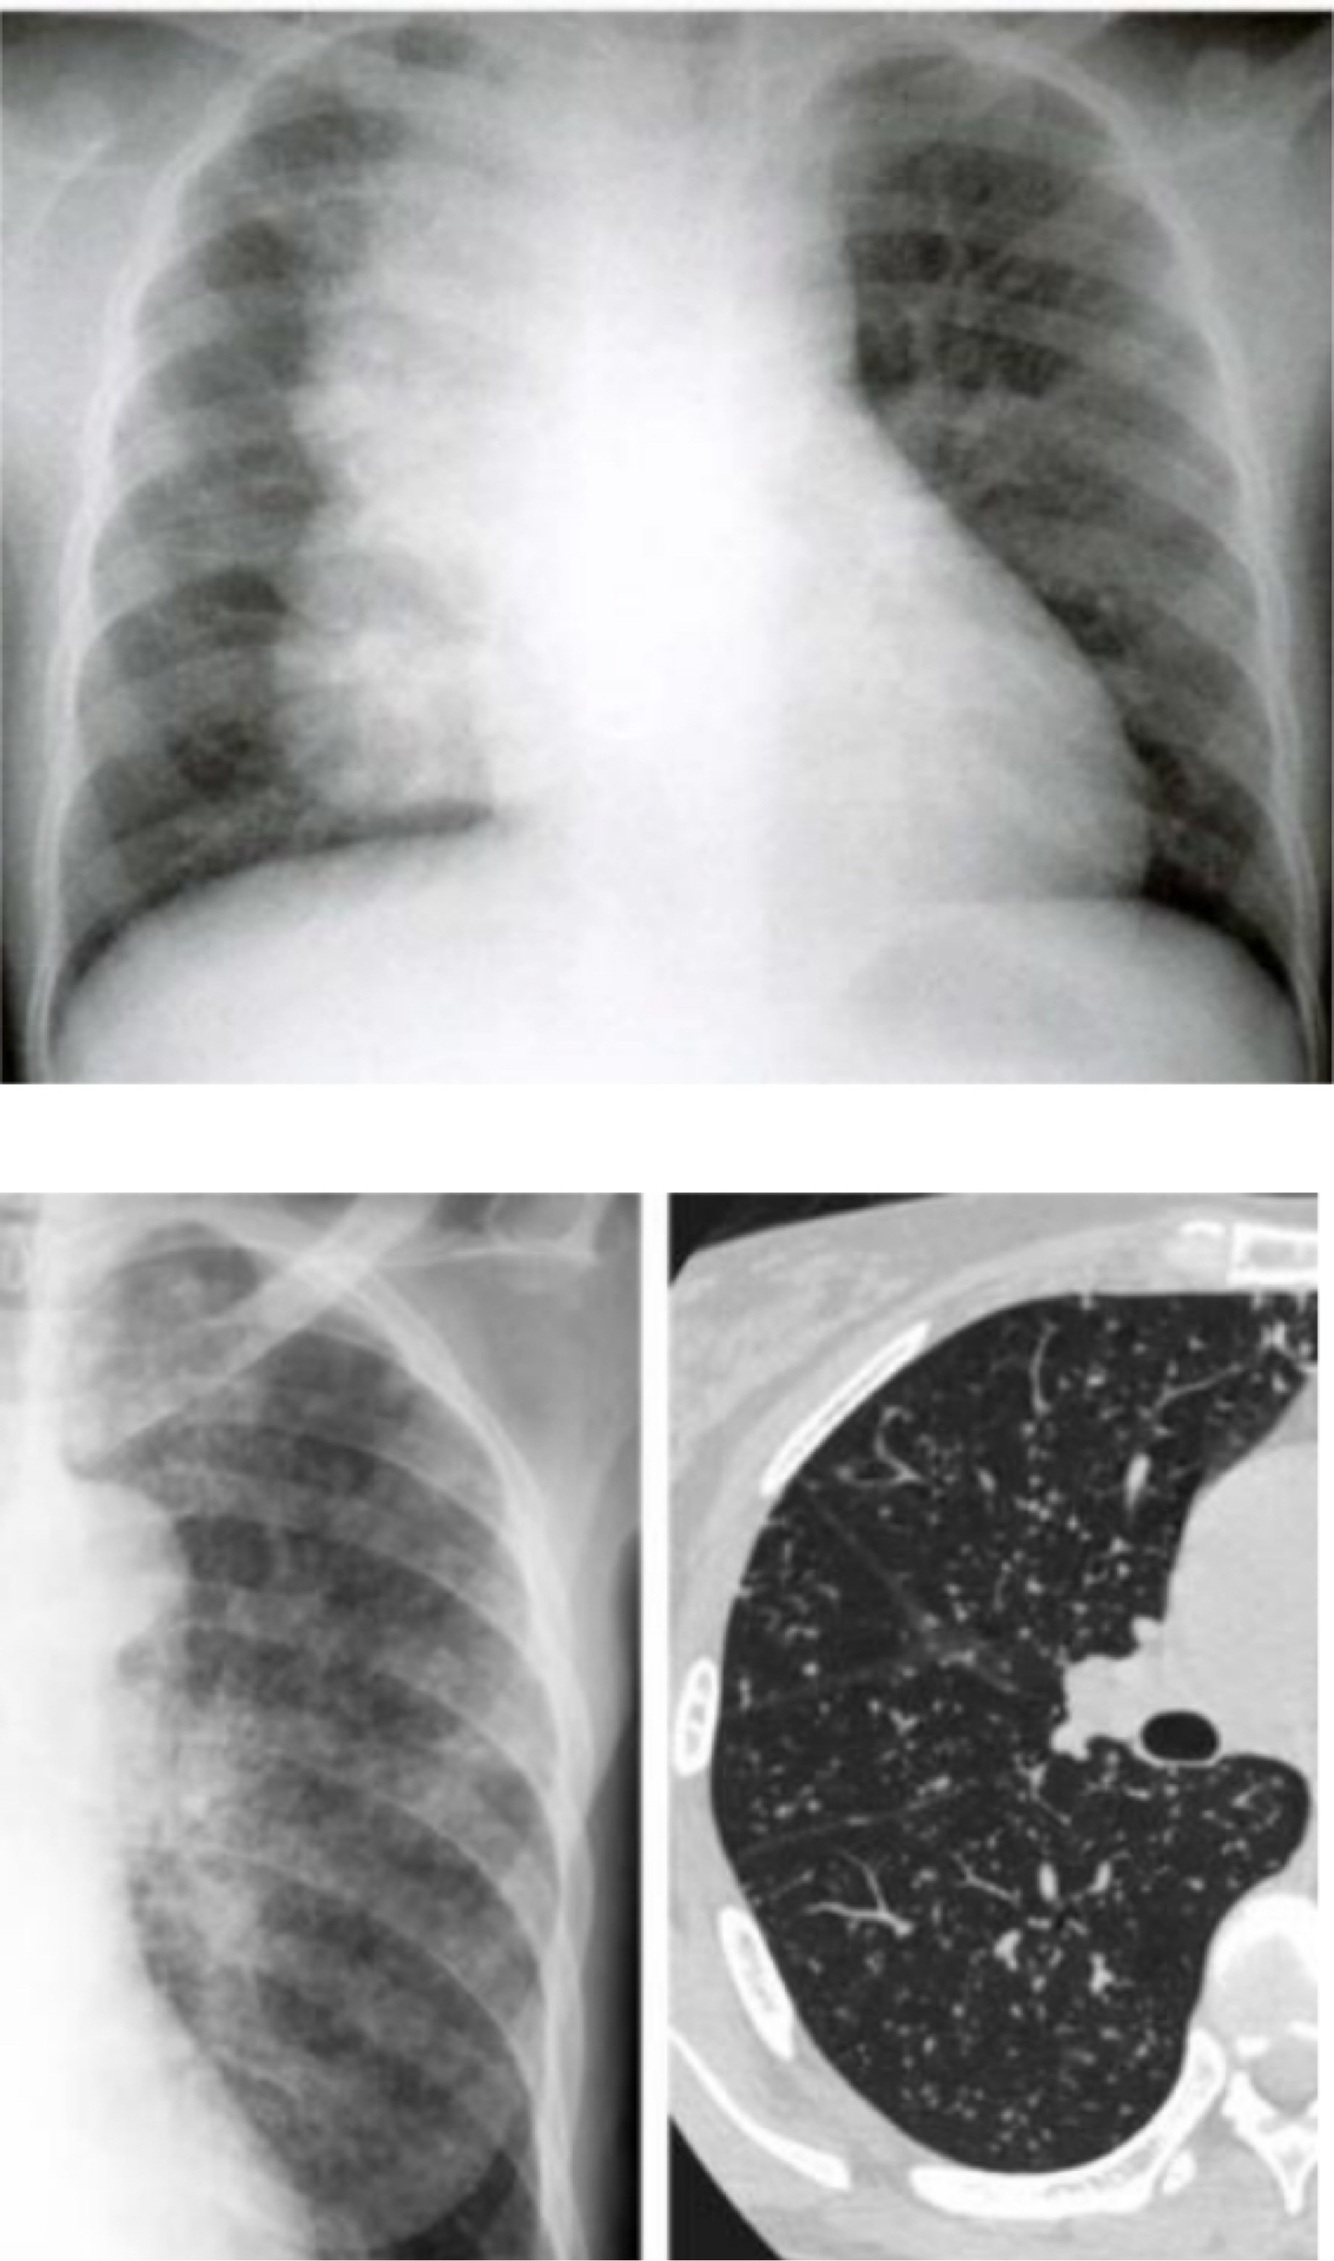

-RX: infiltrado persistente (>2 semanas) + linfonodomegalia hilar ipsilateral.

Adultos e adolescentes.

TB PÓS-PRIMÁRIA – bacilífera :

•Adolescente/adulto – reativação ou reinfecção

•Tosse prolongada, febre vespertina, sudorese noturna, perda de peso

•RX: infiltrado + cavitação

•Complicação: Aspergiloma (bola fúngica)

Tuberculose miliar é um tipo de tuberculose extrapulmonar ?

Sim, a tuberculose miliar é um tipo de tuberculose extrapulmonar. Ela ocorre quando o Mycobacterium tuberculosis se dissemina de forma descontrolada através da corrente sanguínea, afetando múltiplos órgãos fora dos pulmões. Esse tipo de tuberculose é particularmente grave e pode ser semelhante a uma "sepse" devido à sua natureza disseminada. É mais comum em indivíduos imunodeprimidos ou em crianças menores de 2 anos que não foram vacinadas com a BCG. A radiografia de tórax geralmente mostra um infiltrado micronodular difuso bilateral, que se assemelha a pequenas sementes de milho dispersas por todo o campo pulmonar, refletindo a disseminação extensa da infecção.